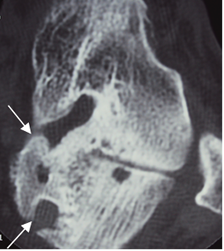

Fig 119 A. Síndrome del seno del tarso.

TAC axial. Cambios degenerativos con formación de osteofitos y puente óseo, en la parte medial de la articulación talocalcánea.